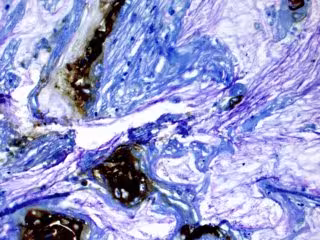

Altos niveles de CO2 en el cuerpo por trastornos respiratorios crónicos pueden e - KOUSHIK DAS, MD - Archivo

Investigaciones anteriores habían demostrado que el microambiente del tumor pancreático alberga niveles aumentados de CO2. Aquí, el equipo demostró que aumentar el CO2 en cultivos celulares a los niveles observados en pacientes pulmonares era suficiente para aumentar su crecimiento y agresividad.